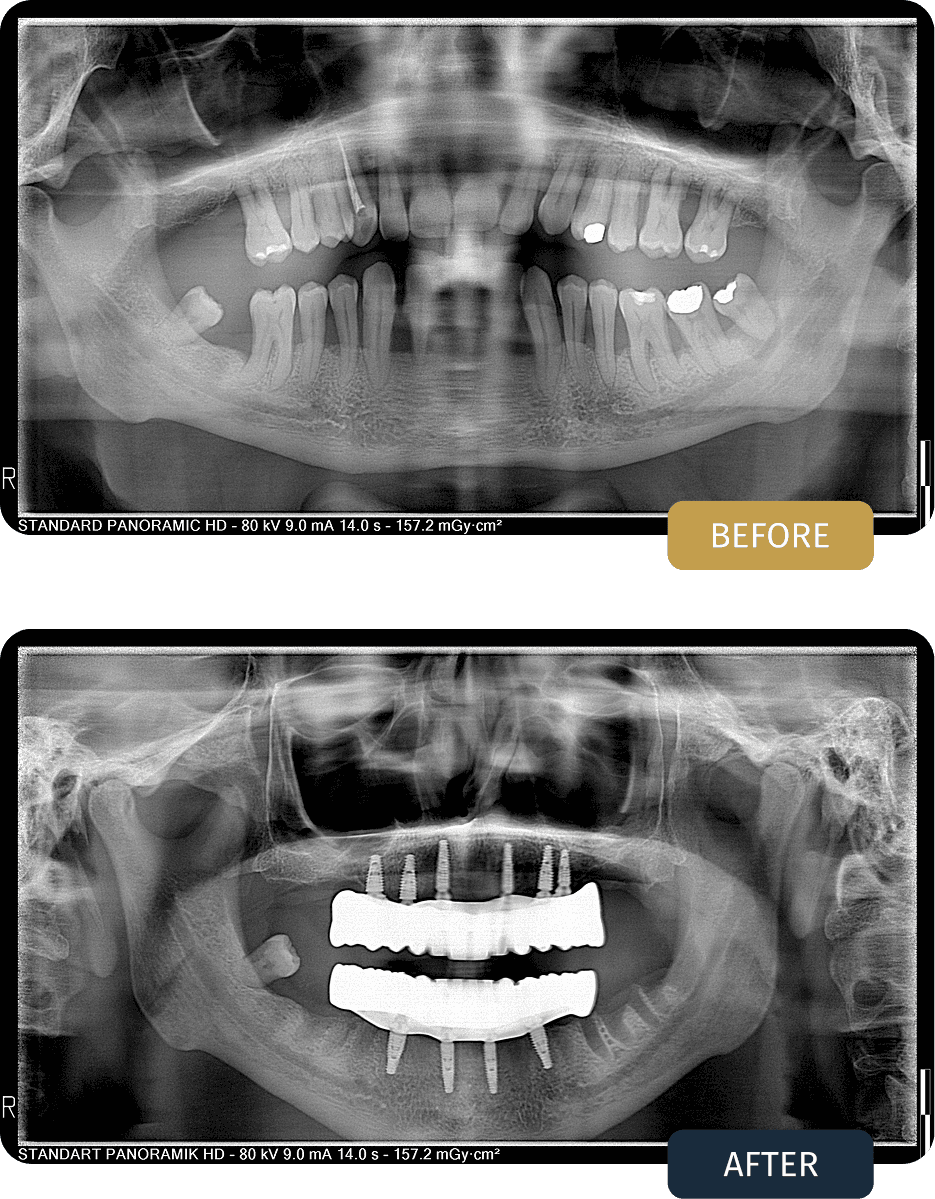

Dean presented with advanced dental deterioration, missing posterior support, and multiple compromised teeth affecting both jaws.

Clinical examination and panoramic imaging confirmed that a full arch implant solution was required in both jaws to restore long term stability, function, and comfort.

Post treatment panoramic imaging confirmed accurate implant positioning in both jaws and stable integration of all implants.

• Upper Jaw: All on 6

• Lower Jaw: All on 4

• Both Jaws: Bar supported fixed prosthesis